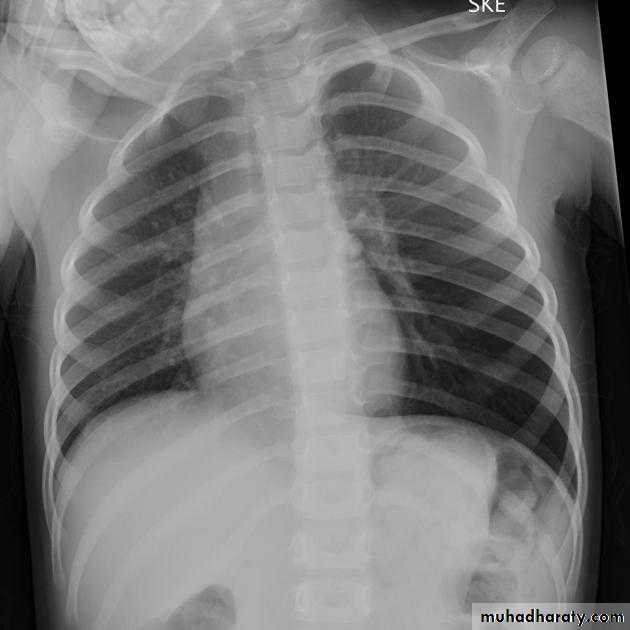

Hydro pnuemothorax

Hydropneumothorax is a term given to the concurrent presence of a pneumothorax as well as a hydrothorax (i.e. air and fluid) in the pleural space.Plain radiographs

On an erect chest radiograph, recognition of hydropneumothorax can be rather easy - and is clasically shown as an air-fluid level. On the supine radiograph, this may be more challenging where a sharp pleural line is bordered by increased opacity lateral to it within the pleural space may sometimes suggest towards the diagnosis